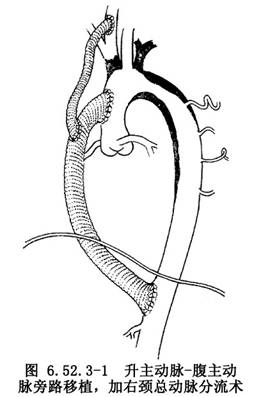

8.無名動脈、左頸總動脈或鎖骨下動脈起源處若亦有狹窄,則應進一步應用主動脈和頭臂動脈分流術,以改善腦部供血。一般選用8mm直徑人造血管,近端吻合口與升主動脈上的人造血管行端-側吻合,遠端經上縱隔引入頸部切口,在狹窄遠端與病變頸動脈做端-側吻合(圖6.52.3-1)。